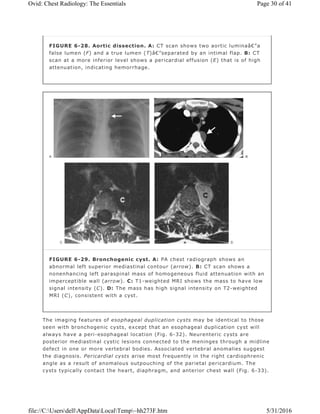

The imaging features of esophageal duplication cysts may be identical to those

seen with bronchogenic cysts, except that an esophageal duplication cyst will

always have a peri-esophageal location (Fig. 6-32). Neurenteric cysts are

posterior mediastinal cystic lesions connected to the meninges through a midline

defect in one or more vertebral bodies. Associated vertebral anomalies suggest

the diagnosis. Pericardial cysts arise most frequently in the right cardiophrenic

angle as a result of anomalous outpouching of the parietal pericardium. The

cysts typically contact the heart, diaphragm, and anterior chest wall (Fig. 6-33).

FIGURE 6-29. Bronchogenic cyst. A: PA chest radiograph shows an

abnormal left superior mediastinal contour (arrow). B: CT scan shows a

nonenhancing left paraspinal mass of homogeneous fluid attenuation with an

imperceptible wall (arrow). C: T1-weighted MRI shows the mass to have low

signal intensity (C). D: The mass has high signal intensity on T2-weighted

MRI (C), consistent with a cyst.